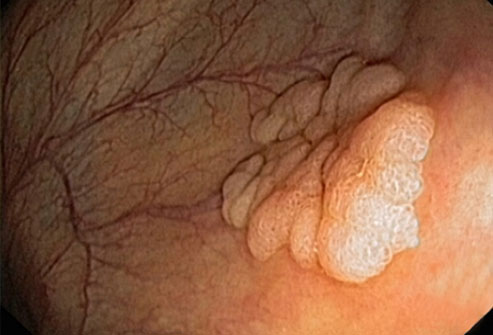

大多数结肠癌是大肠内壁生长的息肉发展而来的。息肉可能是也可能不是癌细胞。如果息肉属于癌细胞,那么癌细胞可能会扩散到身体的其他部位。在息肉癌变前就将其移除,可以完全预防结肠癌。

结直肠癌筛查

结肠镜检查是一种常见的结直肠癌的筛检方法。医生会使用结肠镜进行检查。如果发现息肉,医生可能在检查过程中将其移除。另一种测试是更灵活的乙状结肠镜检查,这种检查只会检查结肠下部。如果你的风险水平属于平均状态,筛查通常从50岁开始进行。